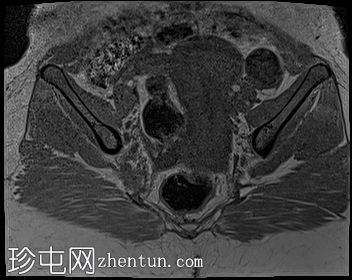

轴位

STIR序列

2.jpg

子宫体积增大,宫底可见息肉样病变,T2加权像呈异常中高信号强度。病变可见轻度扩散受限,增强后呈均匀强化。病变与宫底交界区之间可见一界限清晰的异常高T2信号区域,可能为囊性变性。未见病变超出交界区。

在剖宫产切口远端的前壁上,可见另一处类似的较小病灶。

左侧附件囊性病变,T1加权像信号异常低,T2加权像信号异常高。无增强扫描强化。

子宫内膜息肉是子宫内膜组织的结节状突起。通常表现为T2加权像信号异常高,增强扫描后呈均匀强化。

病理检查通常显示增生期子宫内膜紊乱。